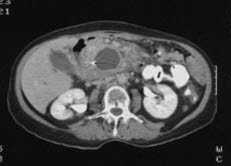

Pseudocyste i bukspyttkjertelenCT er en forkortelse for Computed Tomography. CT bilder dannes av samme type røntgen-stråler som ved vanlig røntgen. CT teknikken skiller seg fra røntgen ved at man benytter en mer avansert metode for å registrere strålene enn vanlig film, og en datamaskin brukes for å sette dataene sammen til et bilde. Røntgenkildene og de delene som fanger opp strålene, røntgen-mottakerne eller detektorene, beveger seg rundt området som avbildes, og muliggjør framstilling i tverrsnitt og tre dimensjoner. Fordelen med denne metoden er at den kan påvise svært små forandringer og den kan fremstille bilder av bløtvevet, i motsetning til røntgen som først og fremst kan fremstille beinvev.

CT-bilder er svarthvite. Organene fremstilles i ulike grader av grått. Vev med lav tetthet, f.eks. luftfylte hulrom, vises som mørke eller svarte partier. Vev med høyere tetthet vises i lysere gråtoner. Jo høyere tetthet, jo lysere. Beinvev fremstilles hvitt.